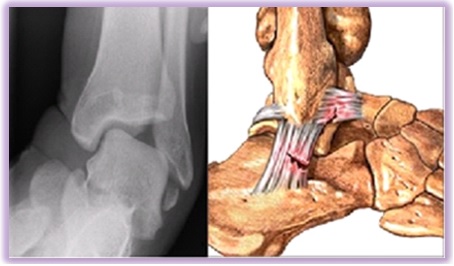

발목인대 파열

보통 발목을 접질릴 때 몸 중심 바깥으로 넘어지는 경우가 많기 때문에 바깥쪽 인대가 파열되면서 그 부위가 붓고 통증이 발생하게 됩니다.

인대가 파열된 부위에서 발생한 출혈이 피하조직으로 퍼져서 넓은 부위에 멍이 들게 됩니다. 멍은 피부 아래에 피가 굳은 것인데 시간이 경과하면 점차 몸속으로 흡수되기 때문에 문제가 없으나 인대가 파열된 것이 문제입니다.

발목인대파열은 발목 상태에 따라 파열부위를 봉합하거나 재건하는 방식으로 진행됩니다.

인대봉합술은 늘어나거나 끊어진 인대와 바깥쪽의 관절주머니를 당겨서 봉합해주는 방법입니다.

발목인대재건술은 관절내시경을 이용해 끊어지거나 늘어난 발목 외측 인대를 다시 튼튼하게 복원하여 발목이 향후 자주 접질리지 않도록 발목을 잡아주는 수술입니다.